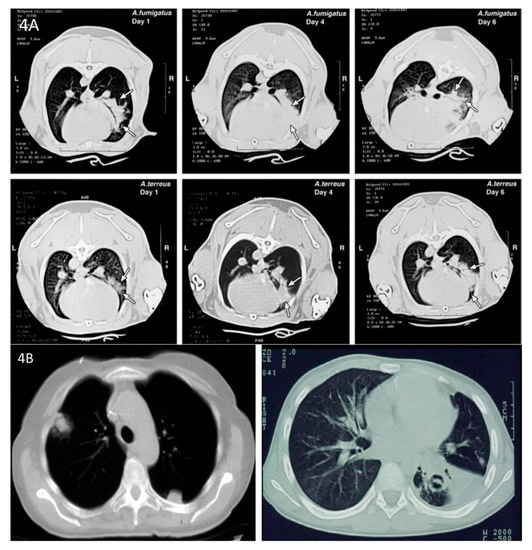

- Walsh, T.J.; Petraitis, V.; Petraitiene, R.; Field-Ridley, A.; Sutton, D.; Ghannoum, M.; Sein, T.; Schaufele, R.; Peter, J.; Bacher, J.; et al. Experimental pulmonary aspergillosis due to Aspergillus terreus: Pathogenesis and treatment of an emerging fungal pathogen resistant to amphotericin B. J. Infect. Dis. 2003, 188, 305–319. [Google Scholar] [CrossRef] [PubMed]